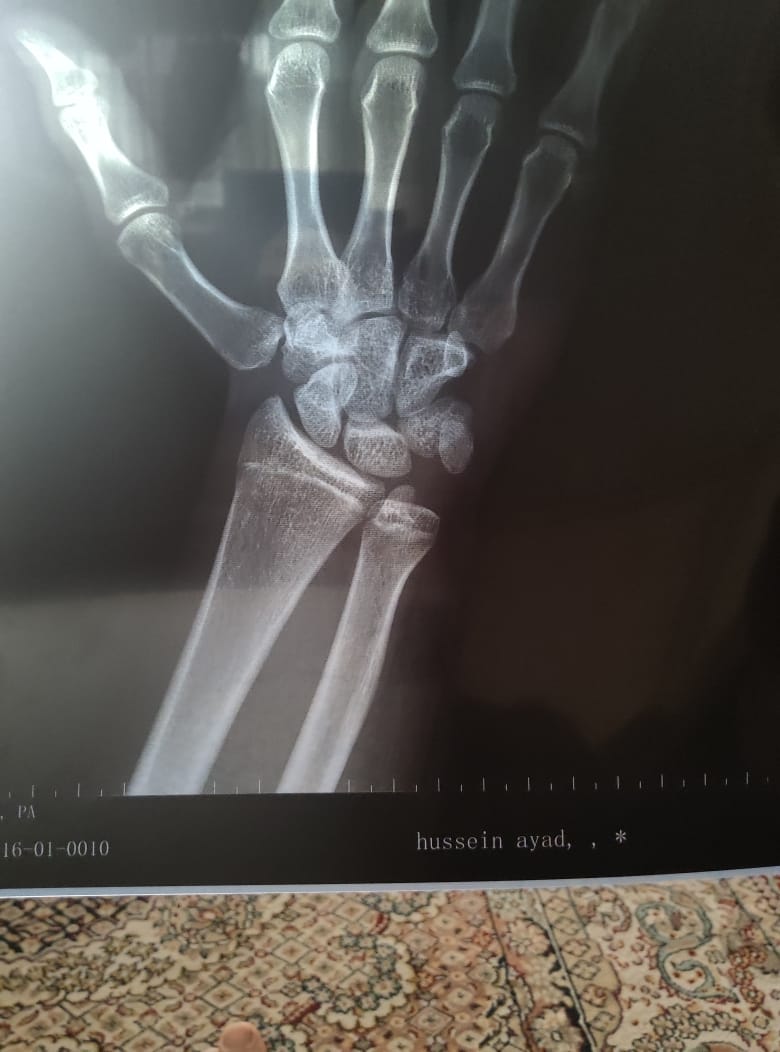

icon 131

عمري 15 و 10 اشهر و هذه اشعة ليدي اليسرى و اريد معرفة هل الصفائح مغلقة او مفتوحة و اريد ايضا معرفة كم المدة الذي من الممكن ان تبقة مفتوحة و كم الزيادة الذي استطيع الحصول عليها من الطول

IMG-20251128-WA0000 ٢٠٢٥١١١٦_٢٠٠٣٣٣